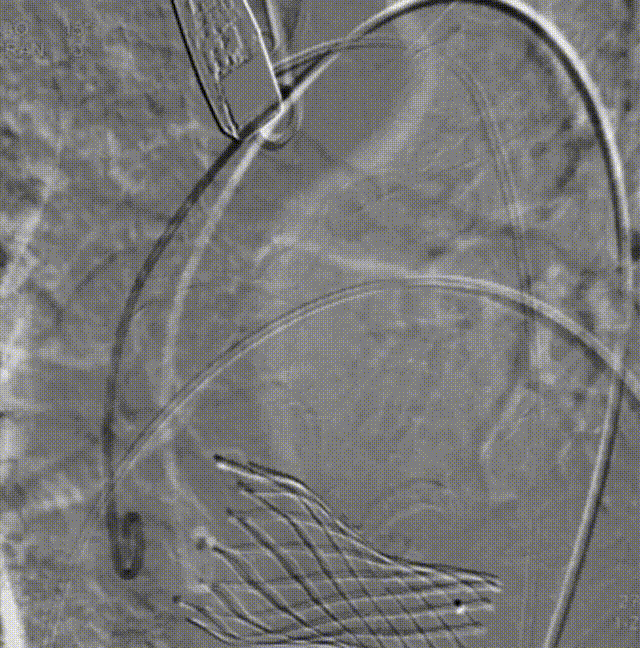

26VenusAplus+snare

瓣膜内22mm球囊后扩张,左冠无显影

LM烟囱支架植入4.0*30mm